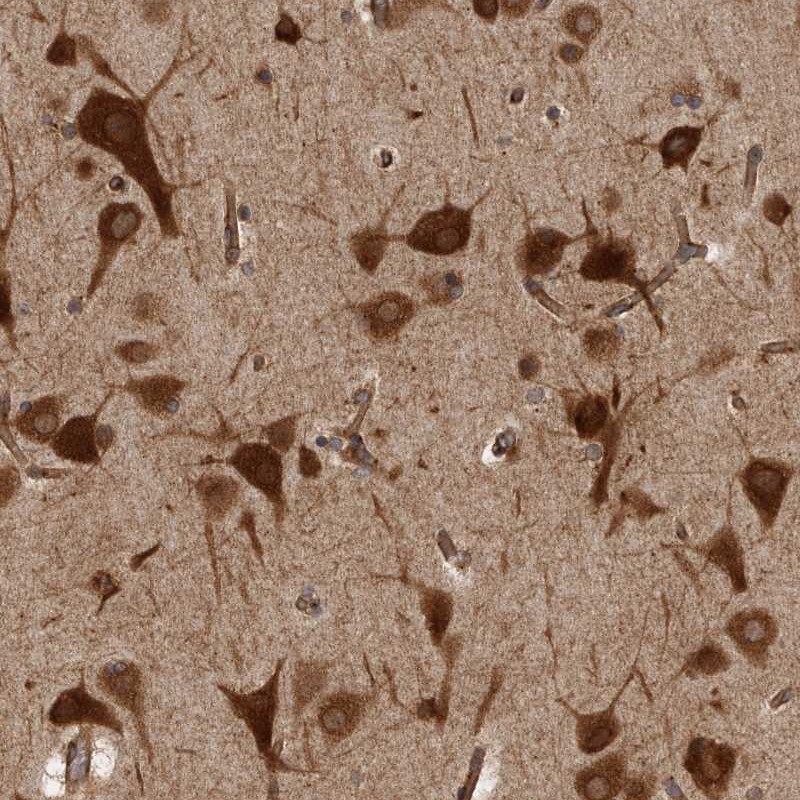

Immunohistochemical staining of human cerebral cortex shows strong cytoplasmic positivity in neuronal cells.